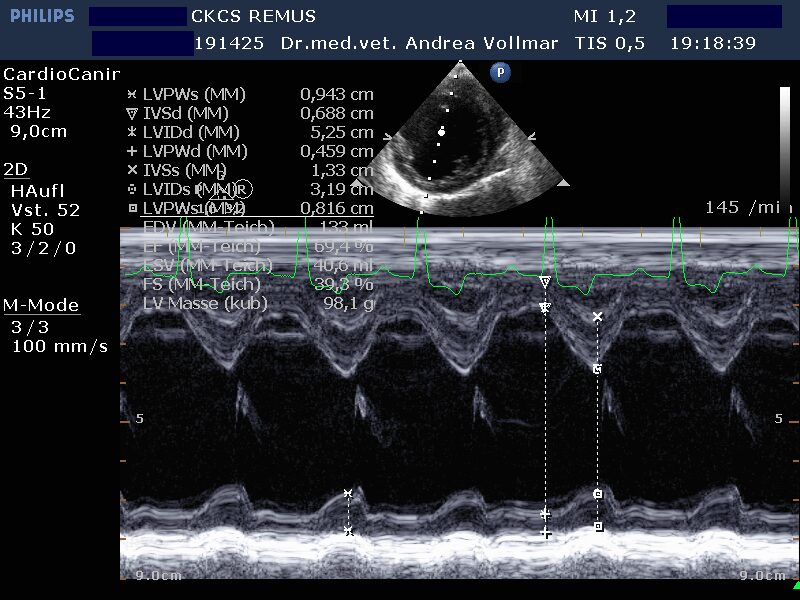

Degenerative Mitralklappeninsuffizienz (MI)

Die degenerative Mitralklappeninsuffizienz (MI) stellt beim Hund die Hauptursache für ein kongestives Herzversagen und kardial bedingten Tod dar. Im Krankheitsverlauf vergrößert sich mit zunehmender Schwere der Klappeninsuffizienz zunehmend der linke Vorhof und das diastolische Ventrikelvolumen nimmt zu, während das systolische Ventrikelvolumen erst mit nachlassender Kontraktilität bei Entwicklung einer Volumenüberlastungskardiomyopathie zunimmt. Bei kleineren Hunden unter 15 kg Körpergewicht ist dies oft erst später im Krankheitsverlauf der Fall, bei größeren Hunden über 15 kg hingegen häufig früher.

Nach derzeitigem Kenntnisstand ist bei MI eine Medikation immer erst dann sinnvoll, wenn bereits eine Herzvergrößerung vorliegt.

Am sichersten kann die Größe der einzelnen Herzabteilungen und der Schweregrad einer AV-Klappeninsuffizienz mit Hilfe der Echokardiografie beurteilt werden. Die Messung der Vorhofgröße vorzugsweise im 2D-Bild korreliert zuverlässig mit dem Ausmaß der MI. Mittels verschiedener Doppler- und Farbdoppler-Analysemethoden kann die Größe der Lücke in der Mitralklappe bestimmt und das regurgitierte Blutvolumen ermittelt werden.